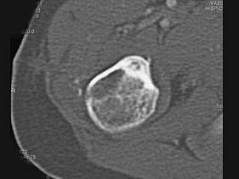

问题 男,28岁,右上肢疼痛,夜间加重,服用止痛药可缓解,结合图像,最可能的诊断是 ( )

选项 A、骨囊肿 B、成骨细胞瘤 C、骨软骨瘤 D、骨样骨瘤 E、骨瘤

答案 D